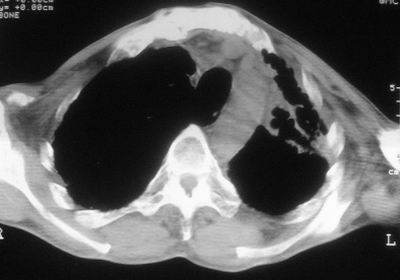

标题: CT11864:男,47岁,反复咳嗽、咯痰、咯血3年,请分析. [打印本页]

患者,男,47岁,反复咳嗽、咯痰、咯血3年,再发5天。痰培养未找到真菌、抗酸杆菌、癌细胞。

左肺上叶体积明显缩小,其内见多发透光区,纵隔向左侧移位,左肺下叶多发班片状病灶,边界模糊,1左肺上叶先天肺发育不全,2左肺下叶肺炎,

左肺上叶结核伴肺纤维化,纵隔移位,左肺下叶感染性病变,建议抗炎抗结核后复查,双肺气肿.

考虑:左肺慢纤伴霉菌球形成、双肺全小叶型肺气肿。

1)考虑为:左肺上叶肺结核(空洞形成),伴左下肺感染;不排除霉菌感染可能。2)肺气肿。

左肺上叶结核伴肺纤维化空洞形成并左肺下叶感染,纵隔牵拉移位,建议作进一步检查排除左侧肺霉菌感染可能。